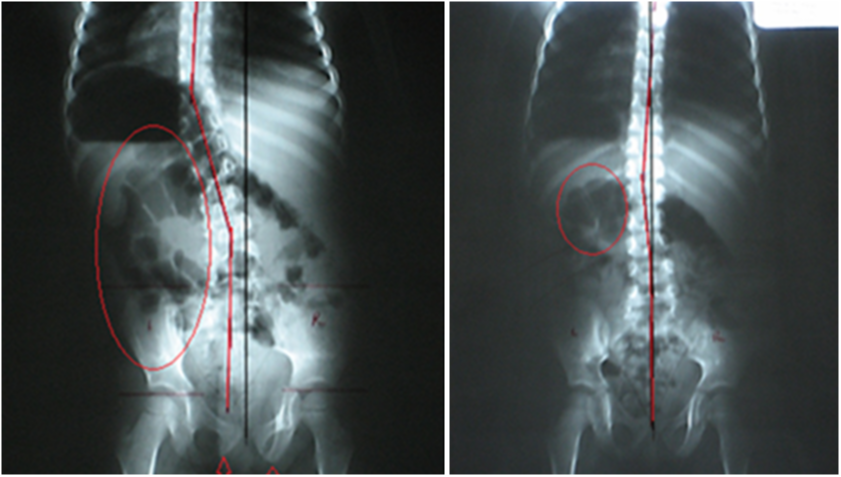

4. SPINAL CORRECTION

You'll get a step-by-step walkthrough Pierce's proprietary subluxation correction method. The hallmark of our subluxation correction is the ability to prove that you've corrected your patient's problem.Â

Our peer-reviewed research shows that our system of spinal subluxation correction is supported by peer-reviewed research, which shows that it produces the fastest and most dramatic post x-ray changes within one to six visits.

To date, there has been no research that demonstrates the effectiveness of rival methodologies.